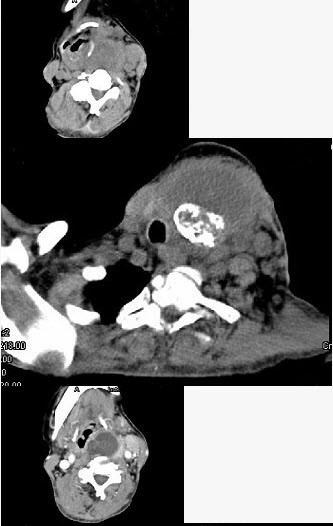

- 单项选择题女,64岁,发现双甲状腺肿大一月余,CT如图所示,最可能诊断为()。

A、结节性甲状腺肿

B、甲状腺腺瘤

C、甲状腺癌并淋巴结转移

D、甲状腺转移癌

E、甲状腺结核

- C